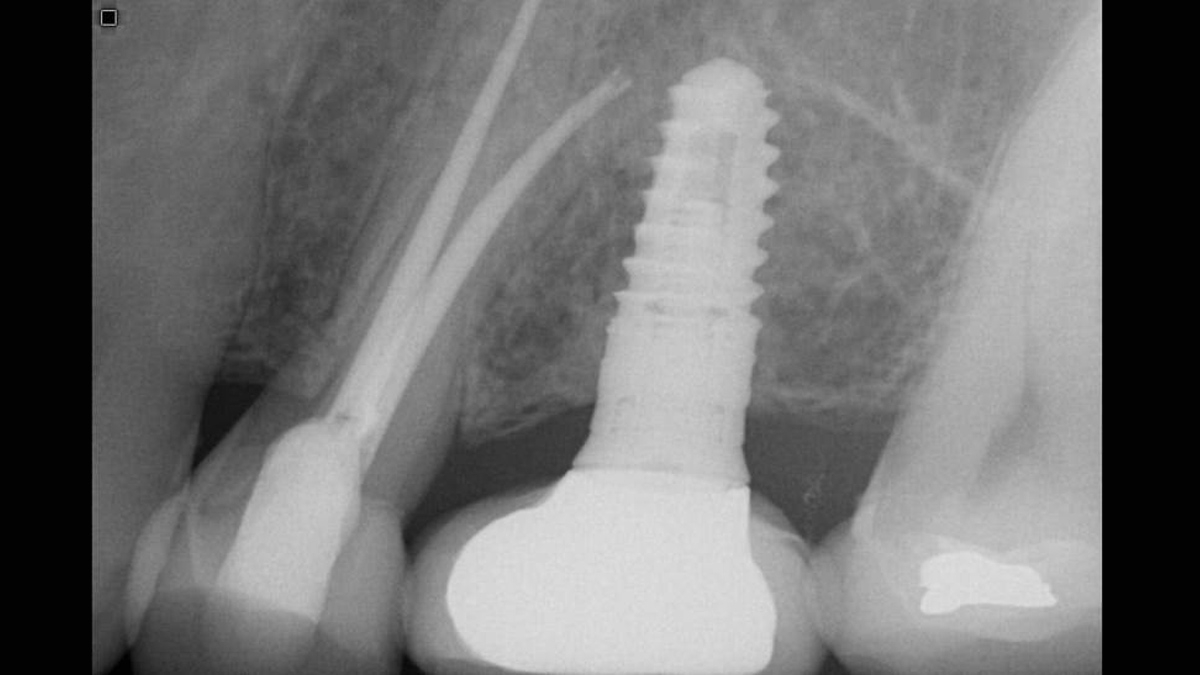

Il sensore Xios XG produce immagini di qualità eccellente. La qualità superiore delle immagini può, da sola, produrre miglioramenti sostanziali nella diagnosi e nell'accettazione da parte del paziente. Grazie alle scelte di sistema più costose, alle capacità di miglioramento dell'immagine e a un team di assistenza eccellente, Xios XG può cambiare il tuo modo di vedere lo studio e l'opinione dei tuoi pazienti.

I sensori Xios XG si integrano perfettamente con gli apparecchi radiografici e il software Dentsply Sirona per una diagnostica intraorale migliore, più sicura e più rapida.